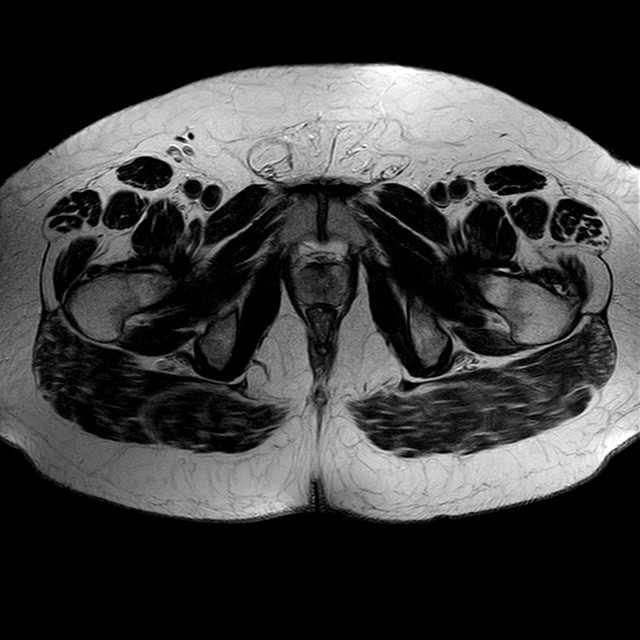

Esami: RMN BACINO

eT2w TSE

Evidenti e simmetriche alterazioni osteofitosiche in regione coxo femorale con riduzione delle rime articolari. Degenerazione completa del cercine glenoideo. Non attuali segni di versamento articolare. Non segni di edema osseo che escludono attuale algodistrofia od osteonecrosi. Lieve e simmetrica riduzione del trofismo della muscolatura glutea.